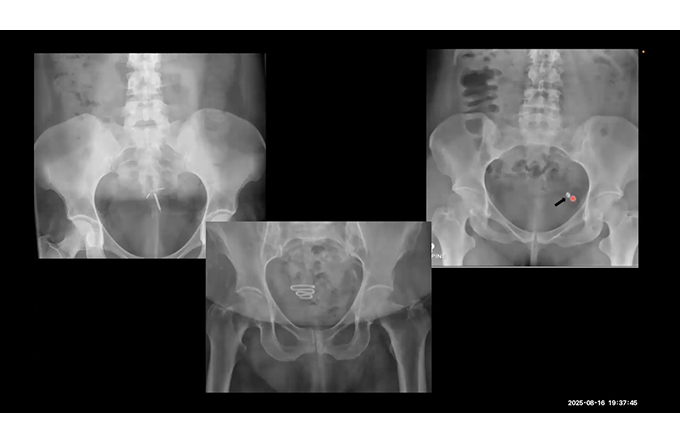

Case based Neuro and Head & Neck Discussion